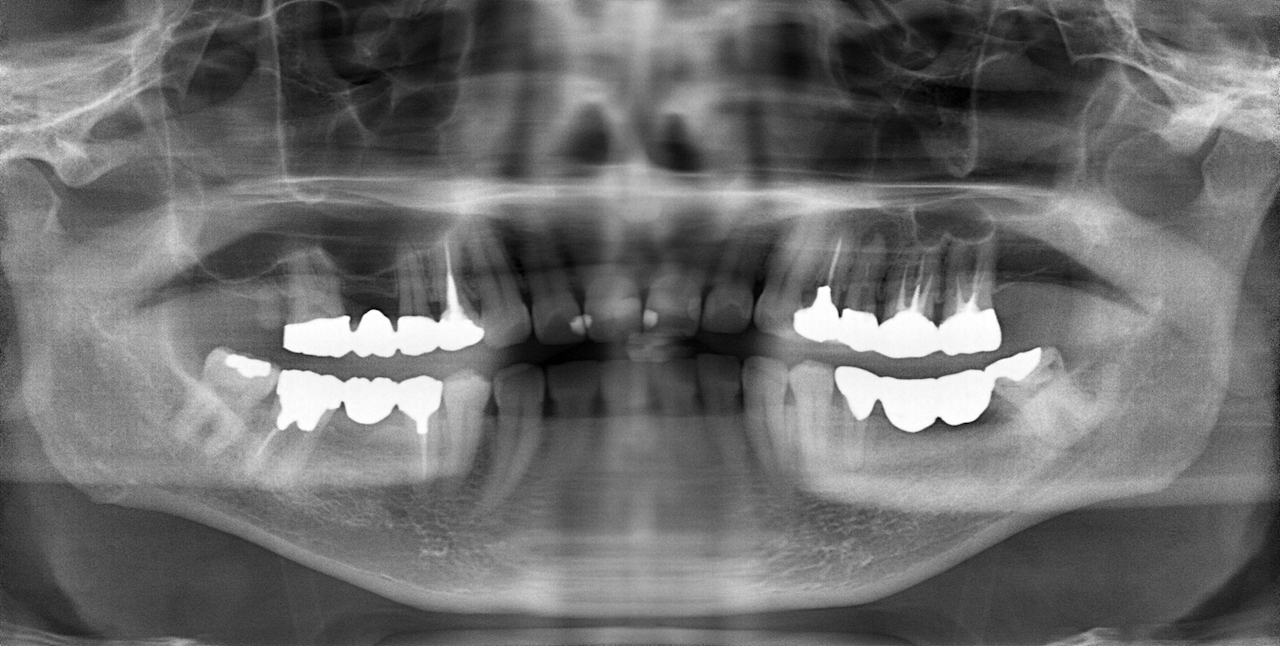

この患者さんは50代の男性で、若い時から様々な歯科治療をなさり、それに伴って抜歯をされたり、咬めなくなったそうです。そのなかで徐々に咬む位置がが分からなくなってきたとい言うお悩みで名取歯科医院にご来院されました。

顎関節の精密検査を行うと顎の状態も左右で異なり、咬み合わせもズレが大きくなったことで歯が欠けるなど、不調の理由がわかりました。

顎関節の軟骨(関節円板)がずれ、それに伴って咬み合わせが変化しても当時の歯科医師が適切な咬み合わせ(咬合調整)しなかったため、そのストレスが長年にわたり顎関節に影響し、痛みを生じてきたと検査から考えられました。

精密検査の中で「T-scan」という咬み合わせの専用の機械を使って診断すると、奥歯以外ではしっかり咬む箇所がなく、明らかに咬み合わせのバランスが良くありません。